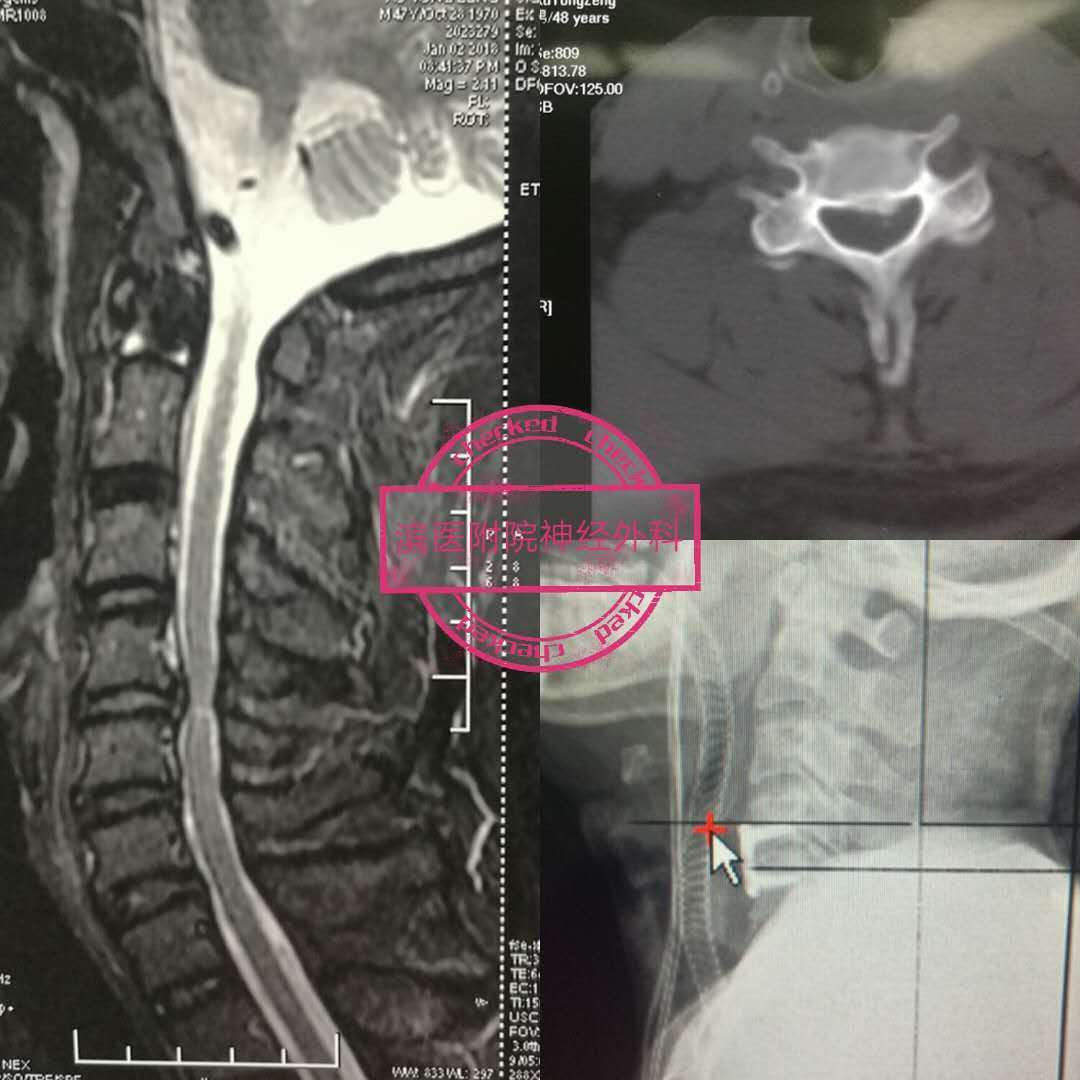

病例:手术治愈多节段颈椎间盘突出症一例

摘除术和微创腰椎间盘完全切除椎间融合固定术等多种手术方法进行治疗

而腰椎间盘突出髓核显微切除术是手术治疗的金标准,小切口,创伤小